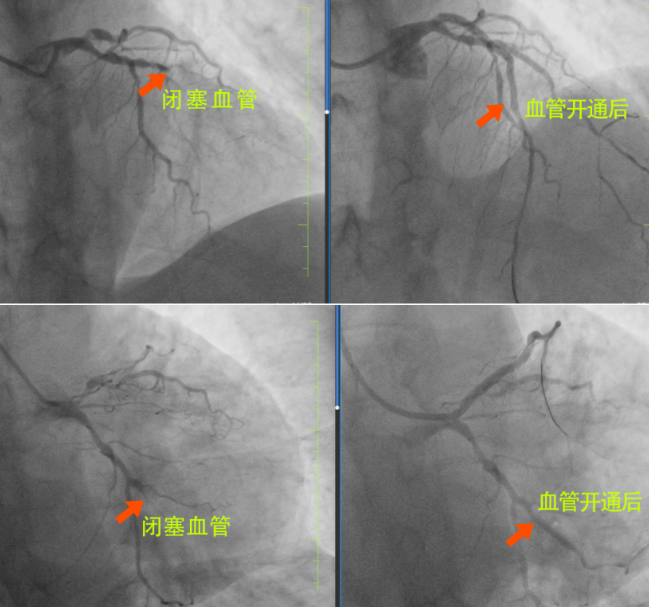

很快,長(zhǎng)春國(guó)文醫(yī)院心內(nèi)科為患者安排了手術(shù),為患者進(jìn)行手術(shù)的是長(zhǎng)春國(guó)文醫(yī)院副院長(zhǎng)、心血管中心主任隋立有。隋院長(zhǎng)在心血管領(lǐng)域造詣深厚,擁有豐富的臨床經(jīng)驗(yàn)。隋院長(zhǎng)始終專注于心血管疾病的研究與治療,對(duì)各類復(fù)雜心血管病例有著獨(dú)到的見解和精準(zhǔn)的判斷。隋院長(zhǎng)在了解患者的病情后,迅速制定了治療方案?;颊?根血管完全閉塞,情況十分危急。但隋院長(zhǎng)憑借著精湛的醫(yī)術(shù)和豐富的經(jīng)驗(yàn),巧妙地開通了2根血管,整個(gè)手術(shù)過程僅僅用了不到半小時(shí),就成功完成了3枚支架的植入。這一高效且精準(zhǔn)的手術(shù),讓患者和家屬驚嘆不已,也讓他們真切地感受到了國(guó)文醫(yī)院心內(nèi)科雄厚的師資力量和成熟的技術(shù)實(shí)力。